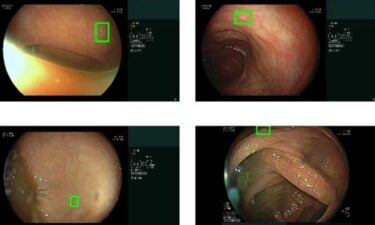

Medizinische Bildanalyse-KIs sollen schnellere und bessere Diagnosen ermöglichen und so die Qualität der medizinischen Vorsorge und Versorgung steigern. Sie werden etwa für die Erkennung von Lungenerkrankungen oder Hauterkrankungen eingesetzt.

Auch bei Bildanalyse-KIs in der Medizin, die anhand medizinischer Bilder Krankheiten diagnostizieren sollen, zeigt sich immer wieder, dass diese Systeme je nach ethnischer Identität der Patienten unterschiedliche Leistungen erbringen.

Die unterschiedliche Leistung der KI-Systeme je nach Ethnizität weisen jedoch laut einer Gruppe KI-Forscher und Mediziner auf ein noch tieferliegendes Problem hin: Die KI-Systeme erkennen die ethnischen Identitäten der Patienten auf den Bildern, ohne dass es für menschliche Experten eine bekannte Korrelation für Ethnizität auf medizinischen Bildern gibt.

In ihrer systematischen Untersuchung zeigen die Forscher außerdem, dass das Problem deutlich größer als angenommen ist: Standard-KI-Systeme können die Ethnizität aus Röntgen- und CT-Bildern mit hoher Leistung vorhersagen und das sogar aus beschädigten, beschnittenen oder verrauschten Bildern und anhand verschiedener Körperregionen.